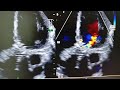

Anatomical Localisation Of Prosthetic Aortic Valve Para Valvular Leakages In TTE